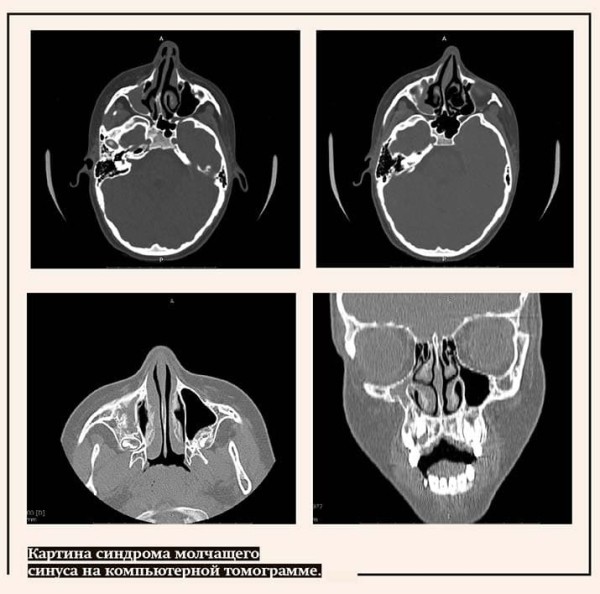

Что касается диагностики, то у синдрома молчащего синуса есть очень характерные черты, по которым его легко определить, глядя на результаты, к примеру, компьютерной томографии. В отличие от любого воспаления, при котором внутри пазухи давление повышено, а значит она увеличена, стенки ее выпучены, при молчащем синусе давление низкое и стенки пазухи вдавлены. Понятно, что и воспаление, и ателектаз могут сочетаться, но снимок все покажет.

Это классический случай обнаружения ателектаза верхнечелюстной пазухи. Даже рентгеновский снимок не всегда может быть достаточно информативным, на нем видно, что пазуха затемнена, но без деталей.

Думаю, только опытный рентгенолог может заподозрить именно ателектаз. В идеале, если подозрение возникло, нужно направить пациента на КТ. К слову, современная конусно-лучевая компьютерная томография по силе облучения сопоставима с обычным рентгеном, но ее информационная ценность гораздо выше.